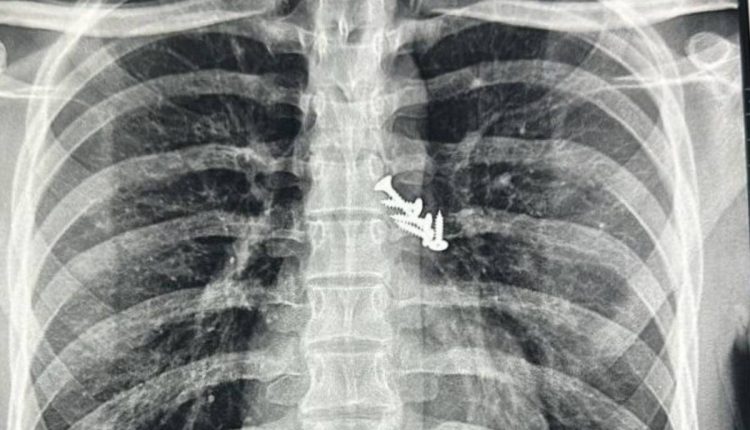

Upon regaining consciousness, the patient experienced a severe bout of coughing lasting 2-3 minutes, followed by persistent cough and chest pain. Diagnostic imaging, including a chest X-ray and plain X-ray of the abdomen, revealed the presence of five screws lodged in the lungs and two screws in the abdomen. Fortunately, screws had not caused any significant tears in the airway.